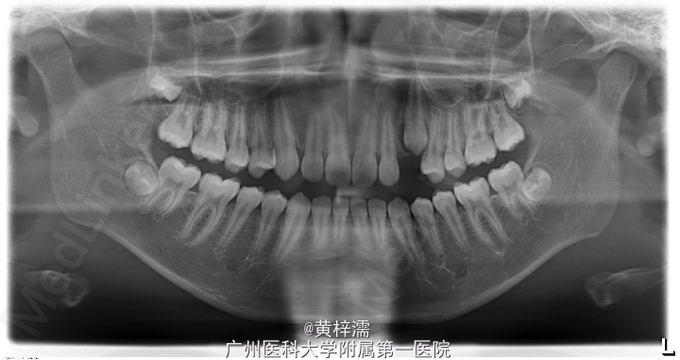

面部基本对称,无露龈笑,笑容不自然。直面型,面中1/3高度与面下1/3高度基本相等。下颌后缩,颏部发育稍不足。上中线与面中线一致,下中线稍右偏0.3mm。左侧磨牙关系中性,无尖牙关系。22,24间前庭沟下方可见鼓起,扪及23,磨牙覆盖正常。右侧磨牙关系中性,尖牙关系1/4远中,磨牙覆盖正常。上牙弓卵圆形,23缺牙间隙8.5mm,13宽度为8.5mm。口腔卫生可,未见牙体、牙周疾病,颞下颌关节检查未见异常。

诊断:安氏ǀ类错牙合;23埋伏阻生牙 处理:选择非拔牙矫治+23外科-正畸导萌术。全口固定正畸治疗,排齐阶段使用双丝技术牵引23,精细调整咬合关系及保持,总疗程18个月。

患者对治疗效果满意,拆除保持器维持1年。讨论:在判断阻生尖牙是否能自行萌出首先需判断阻生牙的倾斜角度及与侧切牙重叠位置,一般阻生超过侧切牙牙根1/2的阻生牙较难自行萌出,第二需要观察尖牙牙根发育状况而定。本患者尖牙已无自行萌出的趋势,因此行正畸牵引。 处理此类阻生尖牙时,首先粘接牵引附件需要确定牵引方向,控制牵引过程牙根不能碰及邻牙;其次牵引阻生牙时,牙列主弓丝必须时硬丝,利用短NITI丝段对阻生牙进行牵引,这样可以避免牵引过程对邻牙产生影响,稳定牙弓。第三,牵引后需要观察牙根方向和轴向,如不佳需要调整为好。